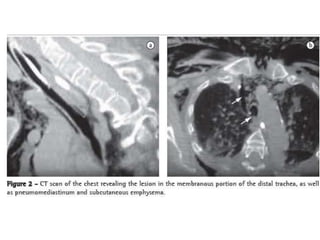

• Enfisema subcutáneo en cuello y tórax 64%

• Neumomediastino

• Neumotorax

Clínica • Enfisema subcutáneoen cuello y tórax 64% • Neumomediastino • Neumotorax • Falla ventilatoria • Dx se confirma con fibrobroncoscopia – Longitud de lesion de 5-13mm